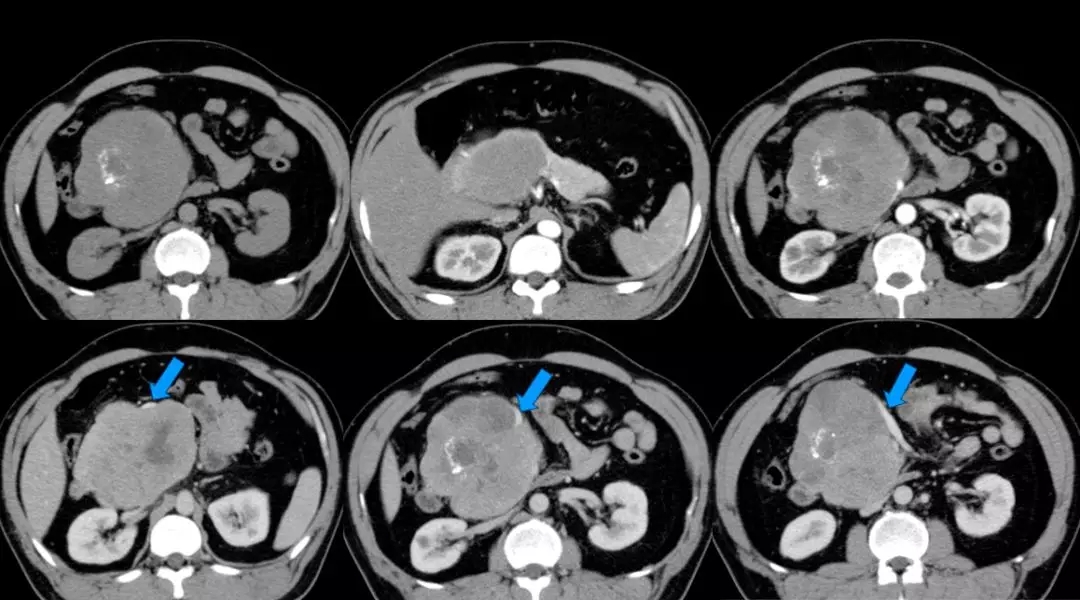

上腹部增强CT:胰头颈体积增大、胰头、颈部可见巨大软组织肿块影,长径约12 cm,与周围分界不清,其内密度不均匀,见片状低密度影及点片状致密影,增强扫描呈不均匀强化,病灶较胰腺实质强化幅度低,其内可见无强化坏死区。腹腔见数个小淋巴结影。脾周可见软组织密度影,长径约1.8 cm,强化方式与脾脏一致。双肾可见多个囊状无强化低密度影。左肺上叶可见斑片状密度增高影,增强可见明显强化。考虑:(1)胰头颈占位,考虑恶性;(2)副脾;(3)双肾多发囊状;(4)左上肺病变,炎症可能。(蓝色箭头为受侵PV-SMV)